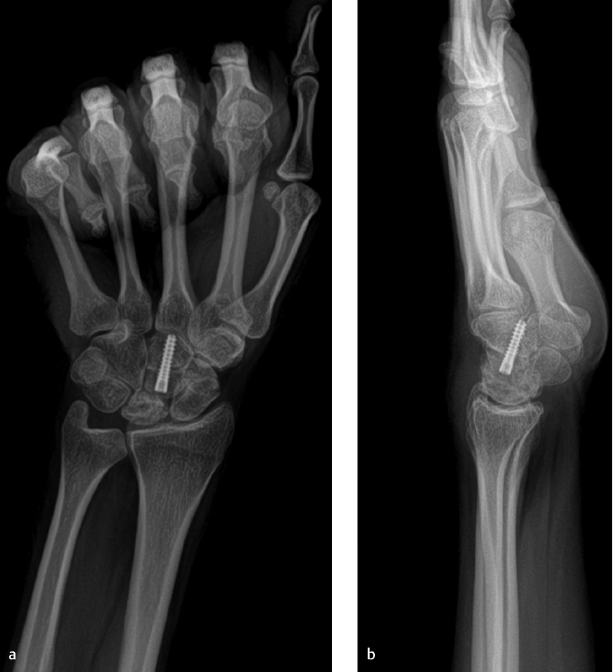

Parallel cuts are then created at the capitate waist with a fine oscillating saw so as to remove a 2-mm wafer of bone. The kerf of the blade should be taken into account when planning the cuts in order to remove the appropriate thickness of bone. The cut surfaces are manually compressed using a blunt instrument inserted into the capitolunate articulation. Fixation of the osteotomy can occur using various methods including K-wires, headless compression screw, or staple. It is the author’s preference to use a headless compression screw placed antegrade (► Fig. 51.1). Wrist flexion aids in presenting the capitate head for placement of the screw, taking care not to distract the osteotomy site with the maneuver. The wound is closed in layers and a short-arm splint is applied which is maintained until the first postoperative visit. At that time, a short-arm cast is applied and is continued until union is confirmed on radiographs, typically in 6 to 8 weeks. Gentle range-of-motion exercises are initiated at that time; however, the wrist remains protected by a removable splint until there is evidence of revascularization of the lunate.